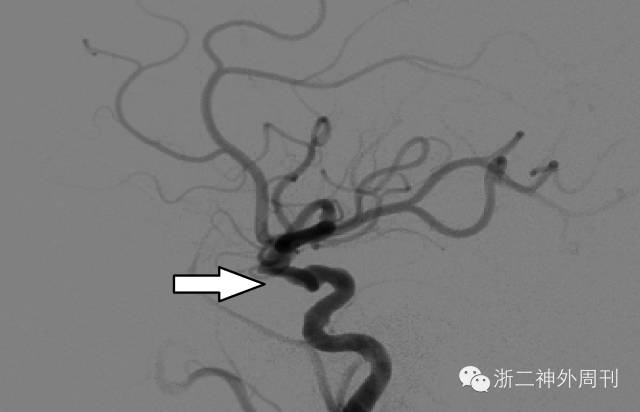

基于上述所见,考虑异物可能伤及颈内动脉,行急诊DSA检查,显示右侧颈内动脉受压变形,动脉壁不光整,未见造影剂外渗(图3)。在导管室临时球囊闭塞颈内动脉下,小心行异物拔除术,撤除临时闭塞球囊后,未见窦道活动性出血。取出的异物为枯竹,测量总长度约为7cm左右,与术前测量长度接近(图4)。将手术情况及还有异物残留可能等告知家属。

图3. DSA检查,显示右侧颈内动脉受压变形,动脉壁不光整。

与家属沟通后,采取后者方案。BOT及加强试验阴性后,行弹簧圈加球囊将右侧颈内动脉及假性动脉瘤一起闭塞(图7)。

图7. 右颈内动脉及假性动脉瘤闭塞,前交通侧枝循环良好。